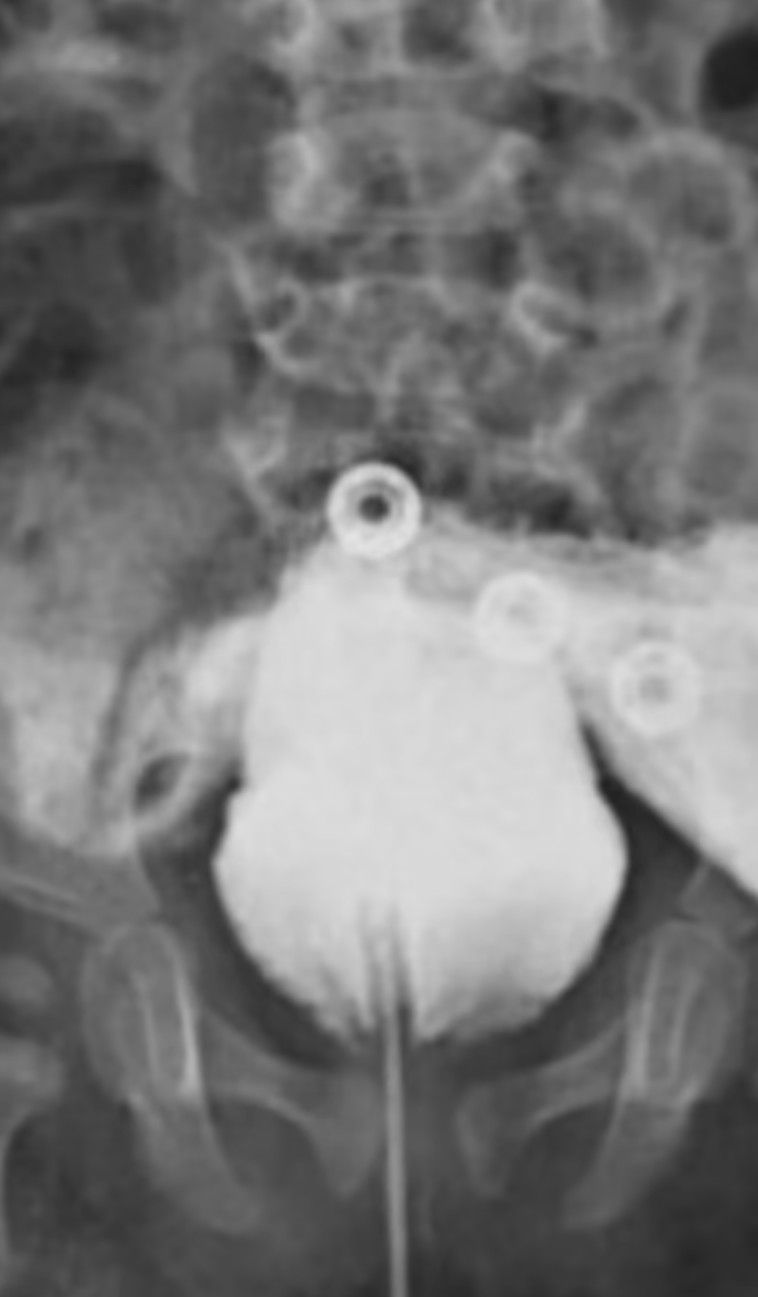

לתינוק, שהיה בן 14 חודשים כאשר המקרה שלו פורסם בכתב העת Radiology Case Reports, היה שק אשכים שלם עם שני אשכים. עם זאת, הוא הטיל שתן דרך פי הטבעת שלו כתוצאה מהמום יוצא הדופן שלו. "אפַליה" מתרחשת כאשר איברי המין אינם מצליחים להתפתח כרגיל ברחם במהלך החודשים הראשונים של ההריון. תהליך דומה גורם לדיפאליה - כאשר זכרים נולדים עם שני איברי מין.

הרופאים טענו שהילד נולד בלידה תקינה ונמצא ב"מצב כללי טוב". אמו, ששמה גם אינו פורסם, לא דיווחה על בעיות במהלך ההריון. בדיקות מיוחדות שבוצעו חודשים לאחר שנולד, אפשרו לרופאים לברר כיצד פועלת מערכת השתן הייחודית שלו. הם גילו פיסטולה, חיבור לא תקין בין שלפוחית השתן שלו לפי הטבעת.